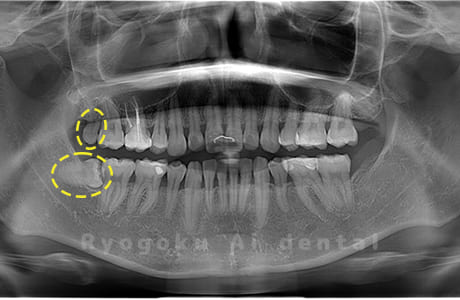

Case09

-

- 原因

- 下顎左の水平埋伏智歯

- 治療内容

- 下顎左の水平埋伏智歯を抜歯したケースです。

<リスク・副作用>

手術後は痛み、腫れ、痺れなどの副作用が生じる場合があります。